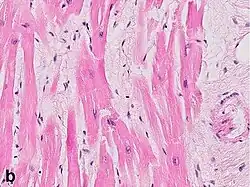

Micrograph of a myocardial infarction (ca. 400x H&E stain ) with prominent contraction band necrosis.

Under the microscope, myocardial infarction presents as a circumscribed area of ischemic, coagulative necrosis (cell death). On gross examination, the infarct is not identifiable within the first 12 hours.[22]

Although earlier changes can be discerned using electron microscopy, one of the earliest changes under a normal microscope are so-called wavy fibers.[23] Subsequently, the myocyte cytoplasm becomes more eosinophilic (pink) and the cells lose their transversal striations, with typical changes and eventually loss of the cell nucleus.[24] The interstitium at the margin of the infarcted area is initially infiltrated with neutrophils, then with lymphocytes and macrophages, who phagocytose ("eat") the myocyte debris. The necrotic area is surrounded and progressively invaded by granulation tissue, which will replace the infarct with a fibrous (collagenous) scar (which are typical steps in wound healing). The interstitial space (the space between cells outside of blood vessels) may be infiltrated with red blood cells.[22]

These features can be recognized in cases where the perfusion was not restored; reperfused infarcts can have other hallmarks, such as contraction band necrosis.[25]